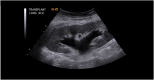

Fig. 1

Renal transplant ultrasound. The renal ultrasound image shows the renal allograft in the right lower quadrant of the abdomen. The allograft measures 12.7 cm in the long axis and demonstrates moderate hydronephrosis.